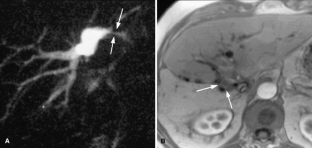

Usual and unusual causes of extrahepatic cholestasis: assessment with magnetic resonance cholangiography and fast MRI

Cholestasis may result from hepatocellular (intrahepatic) disease or biliary tract (extrahepatic) abnormalities. Etiologies causing extrahepatic cholestasis are extremely diverse and invasive procedures, such as endoscopic retrograde cholangiopancreatography (ERCP) and percutaneous transhepatic cholangiography (PTC), were previously required to establish the diagnosis. Due to refinements of magnetic resonance imaging (MRI) techniques, the patient with extrahepatic cholestasis currently can be evaluated noninvasively, and the information revealed frequently exceeds the findings obtained by ERCP and PTC. In this essay, we illustrate the classic MR cholangiographic (MRC) and MRI features of a variety of disorders causing extrahepatic cholestasis, including non-neoplastic disorders of the biliary tract (congenital abnormalities, infectious processes, iatrogenic disorders, and postsurgical complications) and neoplastic conditions (e.g., tumors of the pancreas, biliary tree, liver, ampulla, and regional lymph nodes). In most cases, familiarity with the key MRC features in addition to information obtained via cross-sectional MR images provide sufficient information for adequate lesion characterization.